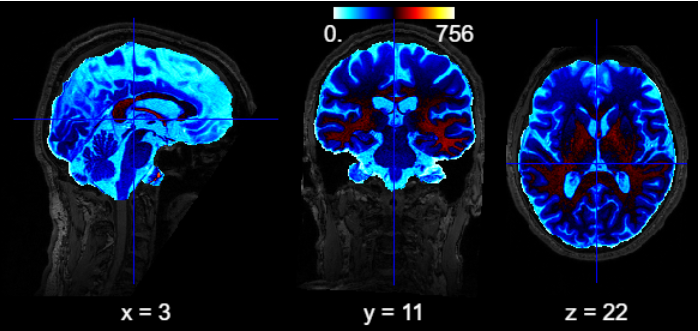

PyBIDS is a Python package that makes it easier to query, summarize, and manage BIDS-formatted datasets. It integrates smoothly with neuroimaging tools like Nipype and Nilearn, which support the BIDS standard natively. Here, you’ll finda more comprehensive example.

BIDSLayout#

layout = BIDSLayout("./bidscointutorial/bids")

all_files = layout.get()

print("There are {} files in the layout.".format(len(all_files)))